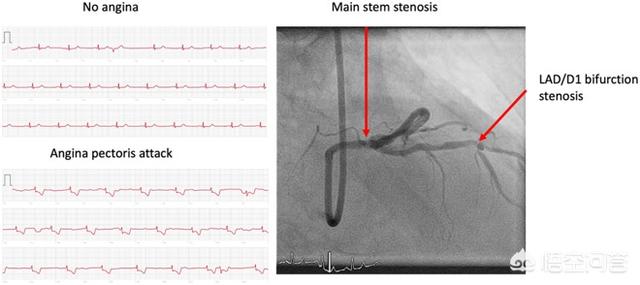

据了解,这名老太太因胸痛、心律不齐和头昏眼花前往美因茨大学医学中心就诊。在医院里,医生们进行了传统的12通道ECG检查,结果显示没有局部缺血的迹象。

然后当这位病人向医生展示了她用Apple Watch做的ECG测试结果,其中可以看到有明显ST段抑制的追踪。医生确实在这些结果中看到了心肌缺血的证据。于是该名病人被转移到了导管实验室,最终发现存在左主干狭窄和左前降支/斜支病变。

于是病人接受了冠状动脉支架植入术并于第二天出院。